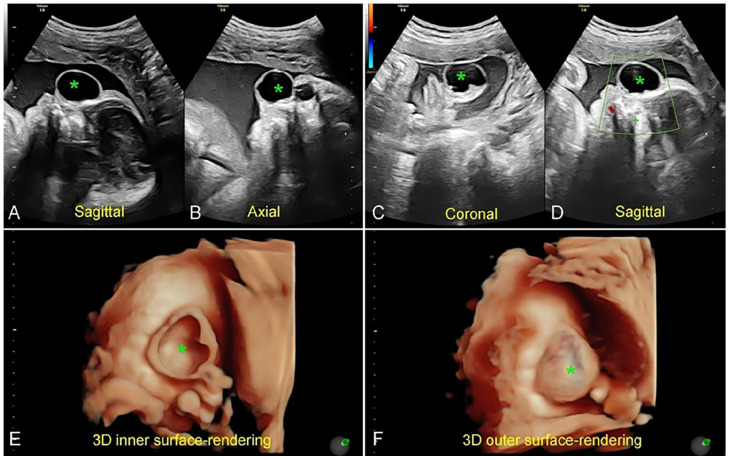

脑膜囊肿是头颅囊肿的一种罕见亚型,可表现为不同位置和不同特征。另一方面,泪囊也是一种罕见的解剖学疾病,通常表现为位于鼻子和眼睛之间的囊肿。一般来说,区分这两种病变并不困难。本病例中,一名胎儿疑似患有泪囊炎,产后最终被诊断为脑膜囊肿,凸显了区分这两种病症的复杂性。文章详细介绍了患者的产前检查、影像学检查结果以及随后的手术干预,强调了细致诊断对有效产前管理的重要性。该病例揭示了与不典型头畸形相关的潜在疏忽和误诊难题,为从事产前诊断和管理的临床医生提供了宝贵的见解。

Meningocele, a rare subtype of cephalocele, can manifest in various positions and exhibit diverse characteristics. On the other hand, dacryocystocele, also a rare anatomical disorder, typically presents as a cyst located between the nose and the eye. Generally, distinguishing between these 2 lesions is not difficult. The presented case involves a fetus with suspected dacryocystocele, ultimately diagnosed postpartum as meningocele, underscoring the complexities in distinguishing between these conditions. The article details the patient's prenatal examinations, imaging findings, and the subsequent surgical intervention, highlighting the significance of meticulous diagnosis for effective prenatal management. The case illuminates the potential oversight and misdiagnosis challenges associated with atypical cephaloceles, contributing valuable insights for clinicians involved in prenatal diagnosis and management.